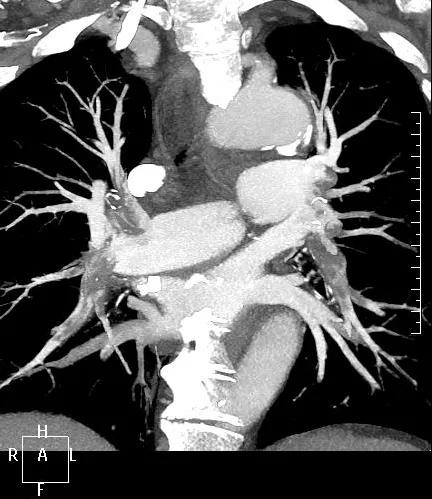

近日,一名港胞翁阿姨在我市突發急性肺栓塞,生命垂危。市二院在接到120出車指令后,迅速響應,患者入院后開通綠色通道,經急診科、心內科、介入科、重癥醫學科等多學科專家開展聯合會診,并于當晚9點行“下腔靜脈、肺動脈造影+導管溶栓+濾器植入術”,患者終于轉危為安,經后續治療與精心護理,病情逐漸穩定,現已轉入普通病房。